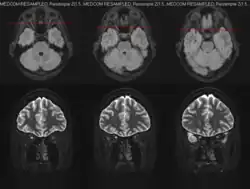

MRT des Sehnervs (axiale und koronale Schnittbilder)